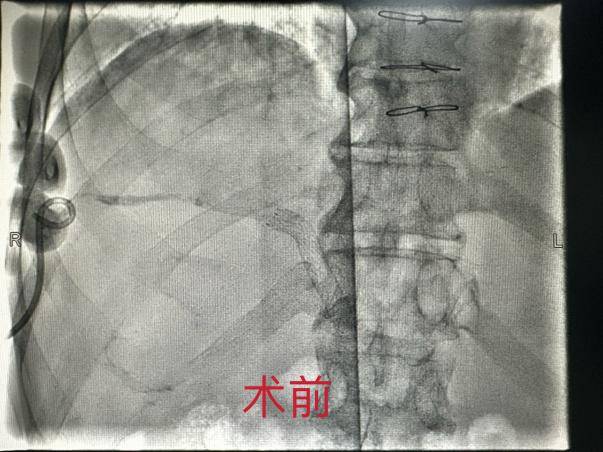

核医学科团队为史先生制定了周密的手术方案,采用“经皮穿肝刺胆管术(PTCD)+胆道放射性粒子植入术”。手术中,医生通过微创手术,成功引流了胆汁,并将30枚放射性碘125粒子精准植入肿瘤部位,对肿瘤进行“精准打击”。术后,史先生的恢复情况良好,肝功能指标基本恢复正常,生活质量得到了显著提升。